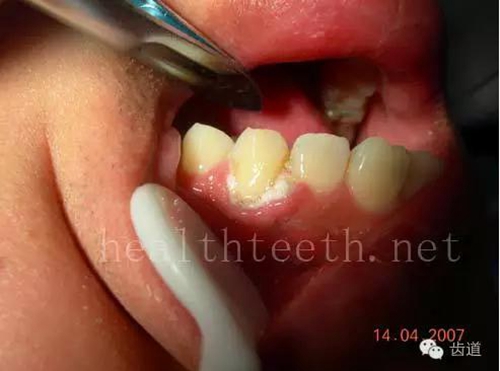

下牙的增生性齦炎,刷牙出血嚴(yán)重

全口牙牙齦炎,出血嚴(yán)重